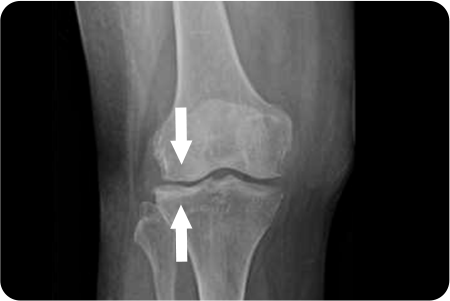

퇴행성관절염으로 연골이 마모되고 관절이 내려앉게 되어

진행된 휜 다리(O 다리, X 다리)를 바르게 교정하여

무릎 내 외측에 집중되어 있는 무게 중심을

고르게 분산시켜 관절염의 진행을 막는 수술법

입니다.